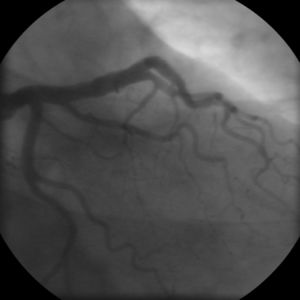

- Coronary angiography

الذبحة المستقرة

In "stable" angina, chest pain with typical features occurring at predictable levels of exertion, various forms of cardiac stress tests may be used to induce both symptoms and detect changes by way of electrocardiography (using an ECG), echocardiography (using ultrasound of the heart) or scintigraphy (using uptake of radionuclide by the heart muscle). If part of the heart seems to receive an insufficient blood supply, coronary angiography may be used to identify stenosis of the coronary arteries and suitability for angioplasty or bypass surgery.[17]

Diagnosis of acute coronary syndrome generally takes place in the emergency department, where ECGs may be performed sequentially to identify "evolving changes" (indicating ongoing damage to the heart muscle). Diagnosis is clear-cut if ECGs show elevation of the "ST segment", which in the context of severe typical chest pain is strongly indicative of an acute myocardial infarction (MI); this is termed a STEMI (ST-elevation MI) and is treated as an emergency with either urgent coronary angiography and percutaneous coronary intervention (angioplasty with or without stent insertion) or with thrombolysis ("clot buster" medication), whichever is available. In the absence of ST-segment elevation, heart damage is detected by cardiac markers (blood tests that identify heart muscle damage). If there is evidence of damage (infarction), the chest pain is attributed to a "non-ST elevation MI" (NSTEMI). If there is no evidence of damage, the term "unstable angina" is used. This process usually necessitates hospital admission and close observation on a coronary care unit for possible complications (such as cardiac arrhythmias – irregularities in the heart rate). Depending on the risk assessment, stress testing or angiography may be used to identify and treat coronary artery disease in patients who have had an NSTEMI or unstable angina.[بحاجة لمصدر]